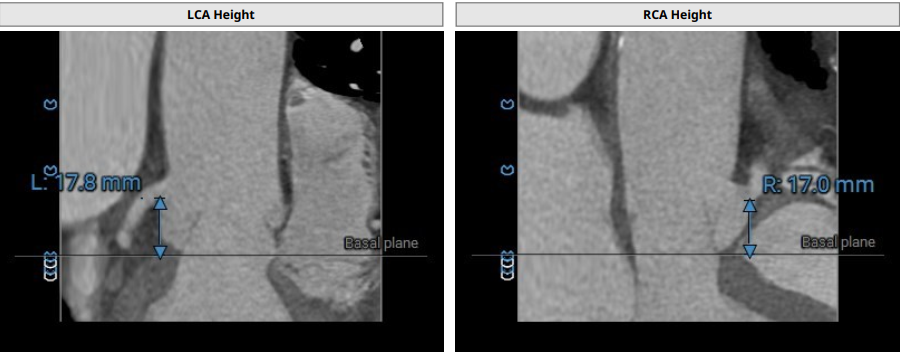

术前影像评估提示,患者为三叶瓣结构,瓣窦分布略显不均,但整体形态规则,无明显钙化负荷。主动脉瓣环直径29.0mm,左心室流出道直径28.5mm,STJ直径34.9mm,升主动脉直径37.9mm,冠脉开口高度充足(左冠17.8mm,右冠17.0 mm)梗阻风险低。

CTA评估(上下滑动查看更多照片)

瓣膜选型:JS/TAVI-31瓣膜